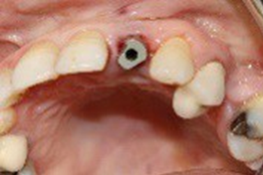

After the 3-month period required for osseointegration of the implant, the patient was seen again (Figure 13) for a digital impression for the definitive prosthesis (using a scan body (Figure 14) and the fabrication of a Ti-base zirconia abutment (Figure 15), noting that the patient was under monthly clinical and radiological control.

Figure 13. Occlusal view of gingival healing

Figure 14. Occlusal view using the bodyscan

Figure 15. Occlusal view of Ti-base zirconia abutment